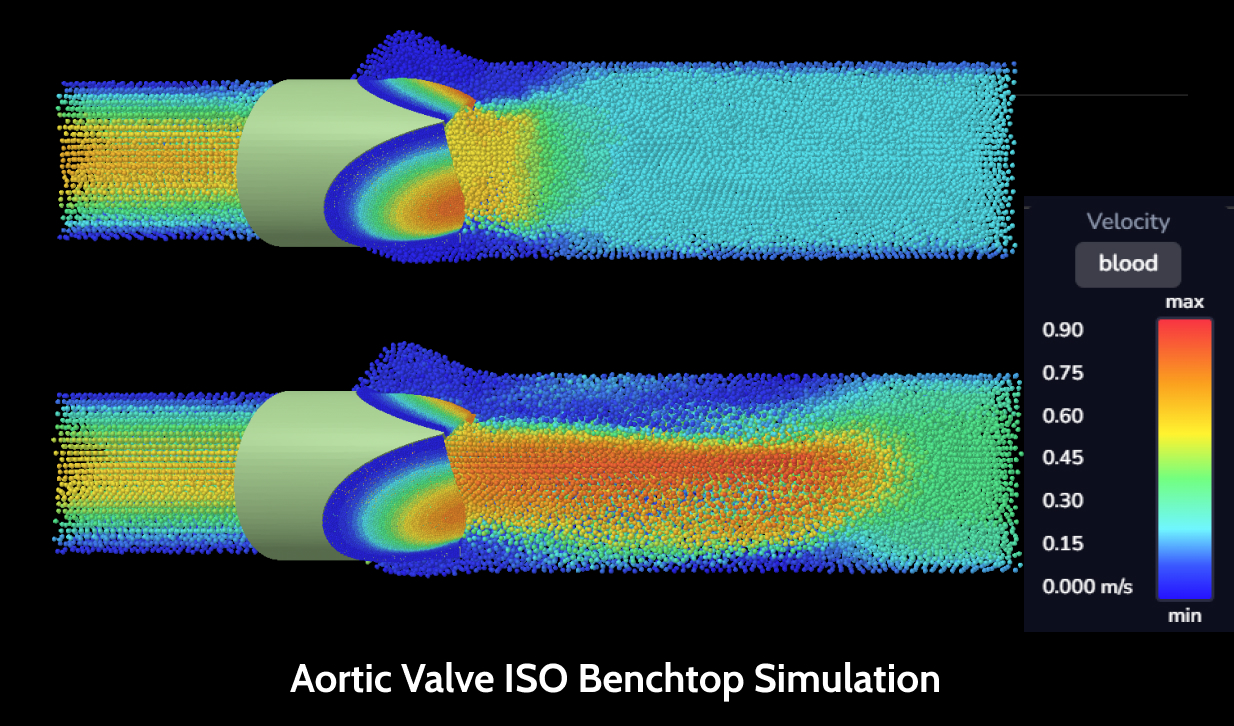

Anatomy study02

Better understand your target anatomy with the help of virtual models, morphological and statistical analysis and simulations.

Advanced anatomical simulations04

Simulate your device in the entire virtual target population to investigate how these body variations may affect the performance and safety of your device.

Data-driven optimization05

Determine the ideal fit of your device and how to adjust your design to treat the maximum number of patients.